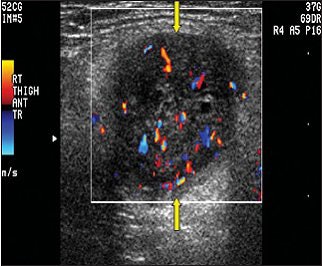

| Schwannoma in a 75-year-old man. Above, color Doppler ultrasonography of the lower anterior leg shows a well-defined oval mass (arrows) with peripheral and central color flow signals, suggesting a hypervascular tumor. Below, neurofibroma in an 84-year-old man. Color Doppler ultrasonography of the right thigh shows a well-defined mass (arrows) with peripheral and central hypervascularity. |

Overall, ultrasound exams did not lead to statistically significant results for making the differential diagnosis, the authors stated. The internal echogenicity was hypoechoic in 100% of the schwannomas and 100% also showed posterior acoustic enhancement. Likewise, 96.2% of the neurofibromas were hypoechoic and 96.2% showed posterior acoustic enhancement. On color Doppler, all showed hypervascular changes. Additional results are shown below.

These results dovetailed with the traditionally held notion that ultrasonography cannot distinguish between the two entities because both are "well-defined solid hypoechoic soft-tissue masses with posterior acoustic enhancement," the authors wrote (Journal of Ultrasound in Medicine, February 2008, Vol. 27:2, pp. 161-166).